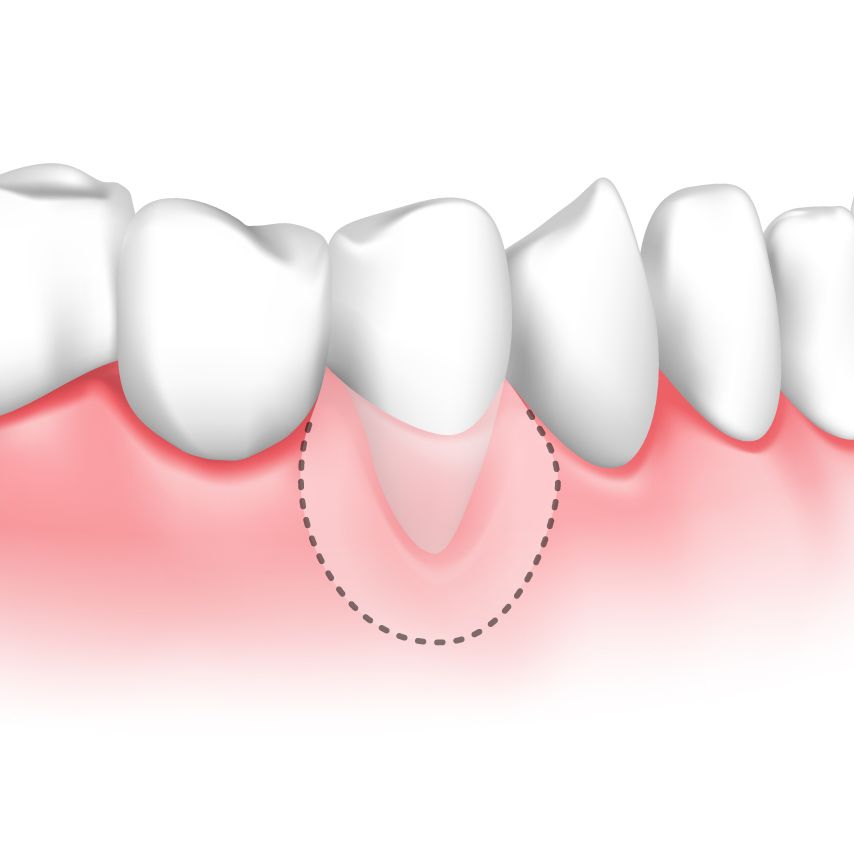

Soft-tissue Grafting

Gum grafting involves transplanting gum tissue to repair a damaged gum line. The procedure can use your own gum tissue from another area of your mouth, donor tissue, or synthetic tissue The tissue is then transplanted to cover your tooth roots, even your gum line, and minimize further recession.